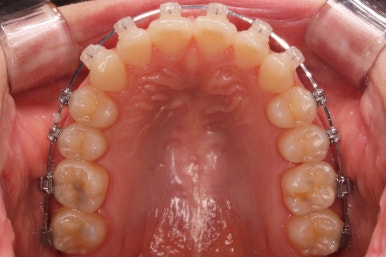

부산부정교합 키다리아저씨치과에 처음 내원하셨을 때의 입안 모습입니다.

위아래 앞니가 삐뚤고 특히 왼쪽 위 송곳니는 밖으로 두드러져 덧니 양상입니다. 윗니는 덧니쪽으로 쏠려 있어서 치열의 중앙이 맞지 않습니다.

전반적인 삐뚤어진 양, 돌출의 느낌, 골격의 비율 등을 고려했을 때 발치 없이 치료를 하기로 했습니다.